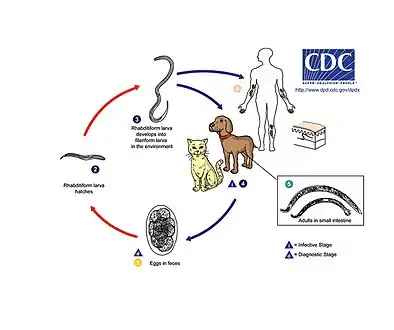

Lifecycle of a hookworm

Lifecycle of a hookworm Cutaneous larvae migrans

Necatoriasis is caused by N. americanus. N. americanus can be divided into two areas – larvae and adult stage. The third stage larvae are guided to human skin by following thermal gradients.[3] Typically, the larvae enter through the hands and feet following contact with contaminated soil. A papular, pruritic, itchy rash will develop around the site of entry into the human host.[4] This is also known as "ground itch". Generally, migration through the lungs is asymptomatic but a mild cough and pharyngeal irritation may occur during larval migration in the airways. Once larvae break through the alveoli and are swallowed, they enter the gastrointestinal tract and attach to the intestinal mucosa where they mature into adult worms. The hookworms attach to the mucosal lining using their cutting plates which allows them to penetrate blood vessels and feed on the host's blood supply. Each worm consumes 30 μl of blood per day. The major issue results from this intestinal blood loss which can lead to iron-deficiency anemia in moderate to heavy infections. Other common symptoms include epigastric pain and tenderness, nausea, exertional dyspnea, pain in lower extremities and in joints, sternal pain, headache, fatigue, and impotence.[5] Death is rare in humans.

Necator americanus was first discovered in Brazil and then was found in Texas. Later, it was found to be indigenous in Africa, China, southwest Pacific islands, India, and Southeast Asia. This parasite is a tropical parasite and is the most common species in humans. Roughly 95% of hookworms found in the southern region of the United States are N. americanus. This parasite is found in humans, but can also be found in pigs and dogs.

Transmission of N. americanus infection requires the deposition of egg-containing feces on shady, well-drained soil and is favored by warm, humid (tropical) conditions. Therefore, infections worldwide are usually reported in places where direct contact with contaminated soil occurs.